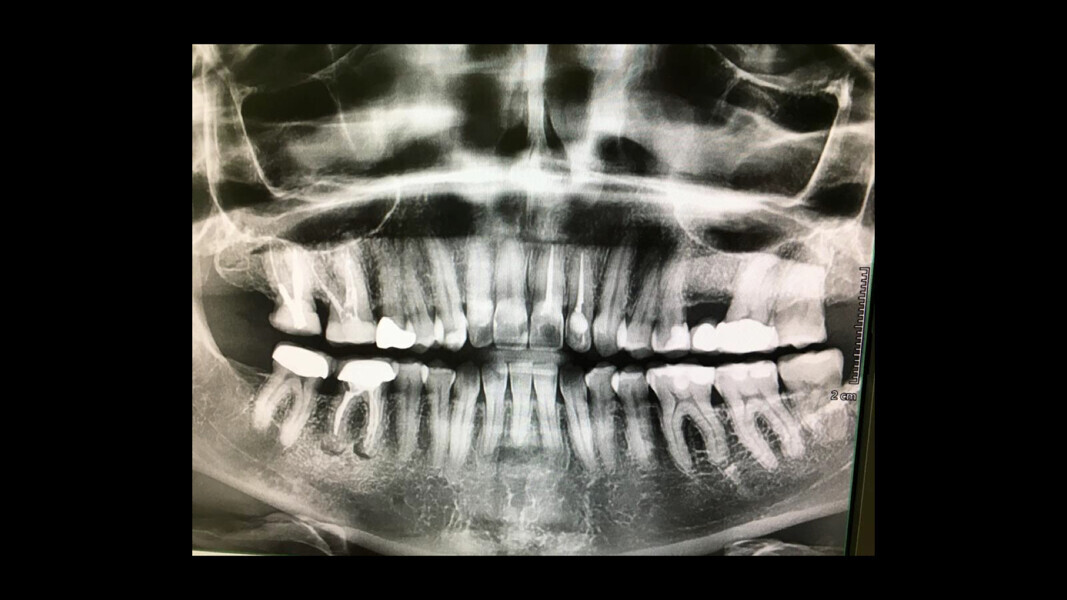

Panoramic radiograph showing a minor apical infection of the mandibular right first molar and endodontic treatment. (All images: Dr Philippe Sleiman and Prof. Ibrahim Nasseh)

In this first case, the patient, who lived abroad and was unable to travel at the time, had swelling of her right mandible (Fig. 6), had had breast cancer and had been under bisphosphonate treatment for 18 months. She sent a panoramic radiograph (Fig. 7), and this showed a minor apical infection of the mandibular right first molar, which had undergone endodontic treatment. A CBCT scan was then taken, and from examining her scan, we could clearly see an area of bone densification (Fig. 8). This should be a red flag because this indicates the start of bone necrosis.

7: Panoramic radiograph showing a minor apical infection of the mandibular right first molar and endodontic treatment.